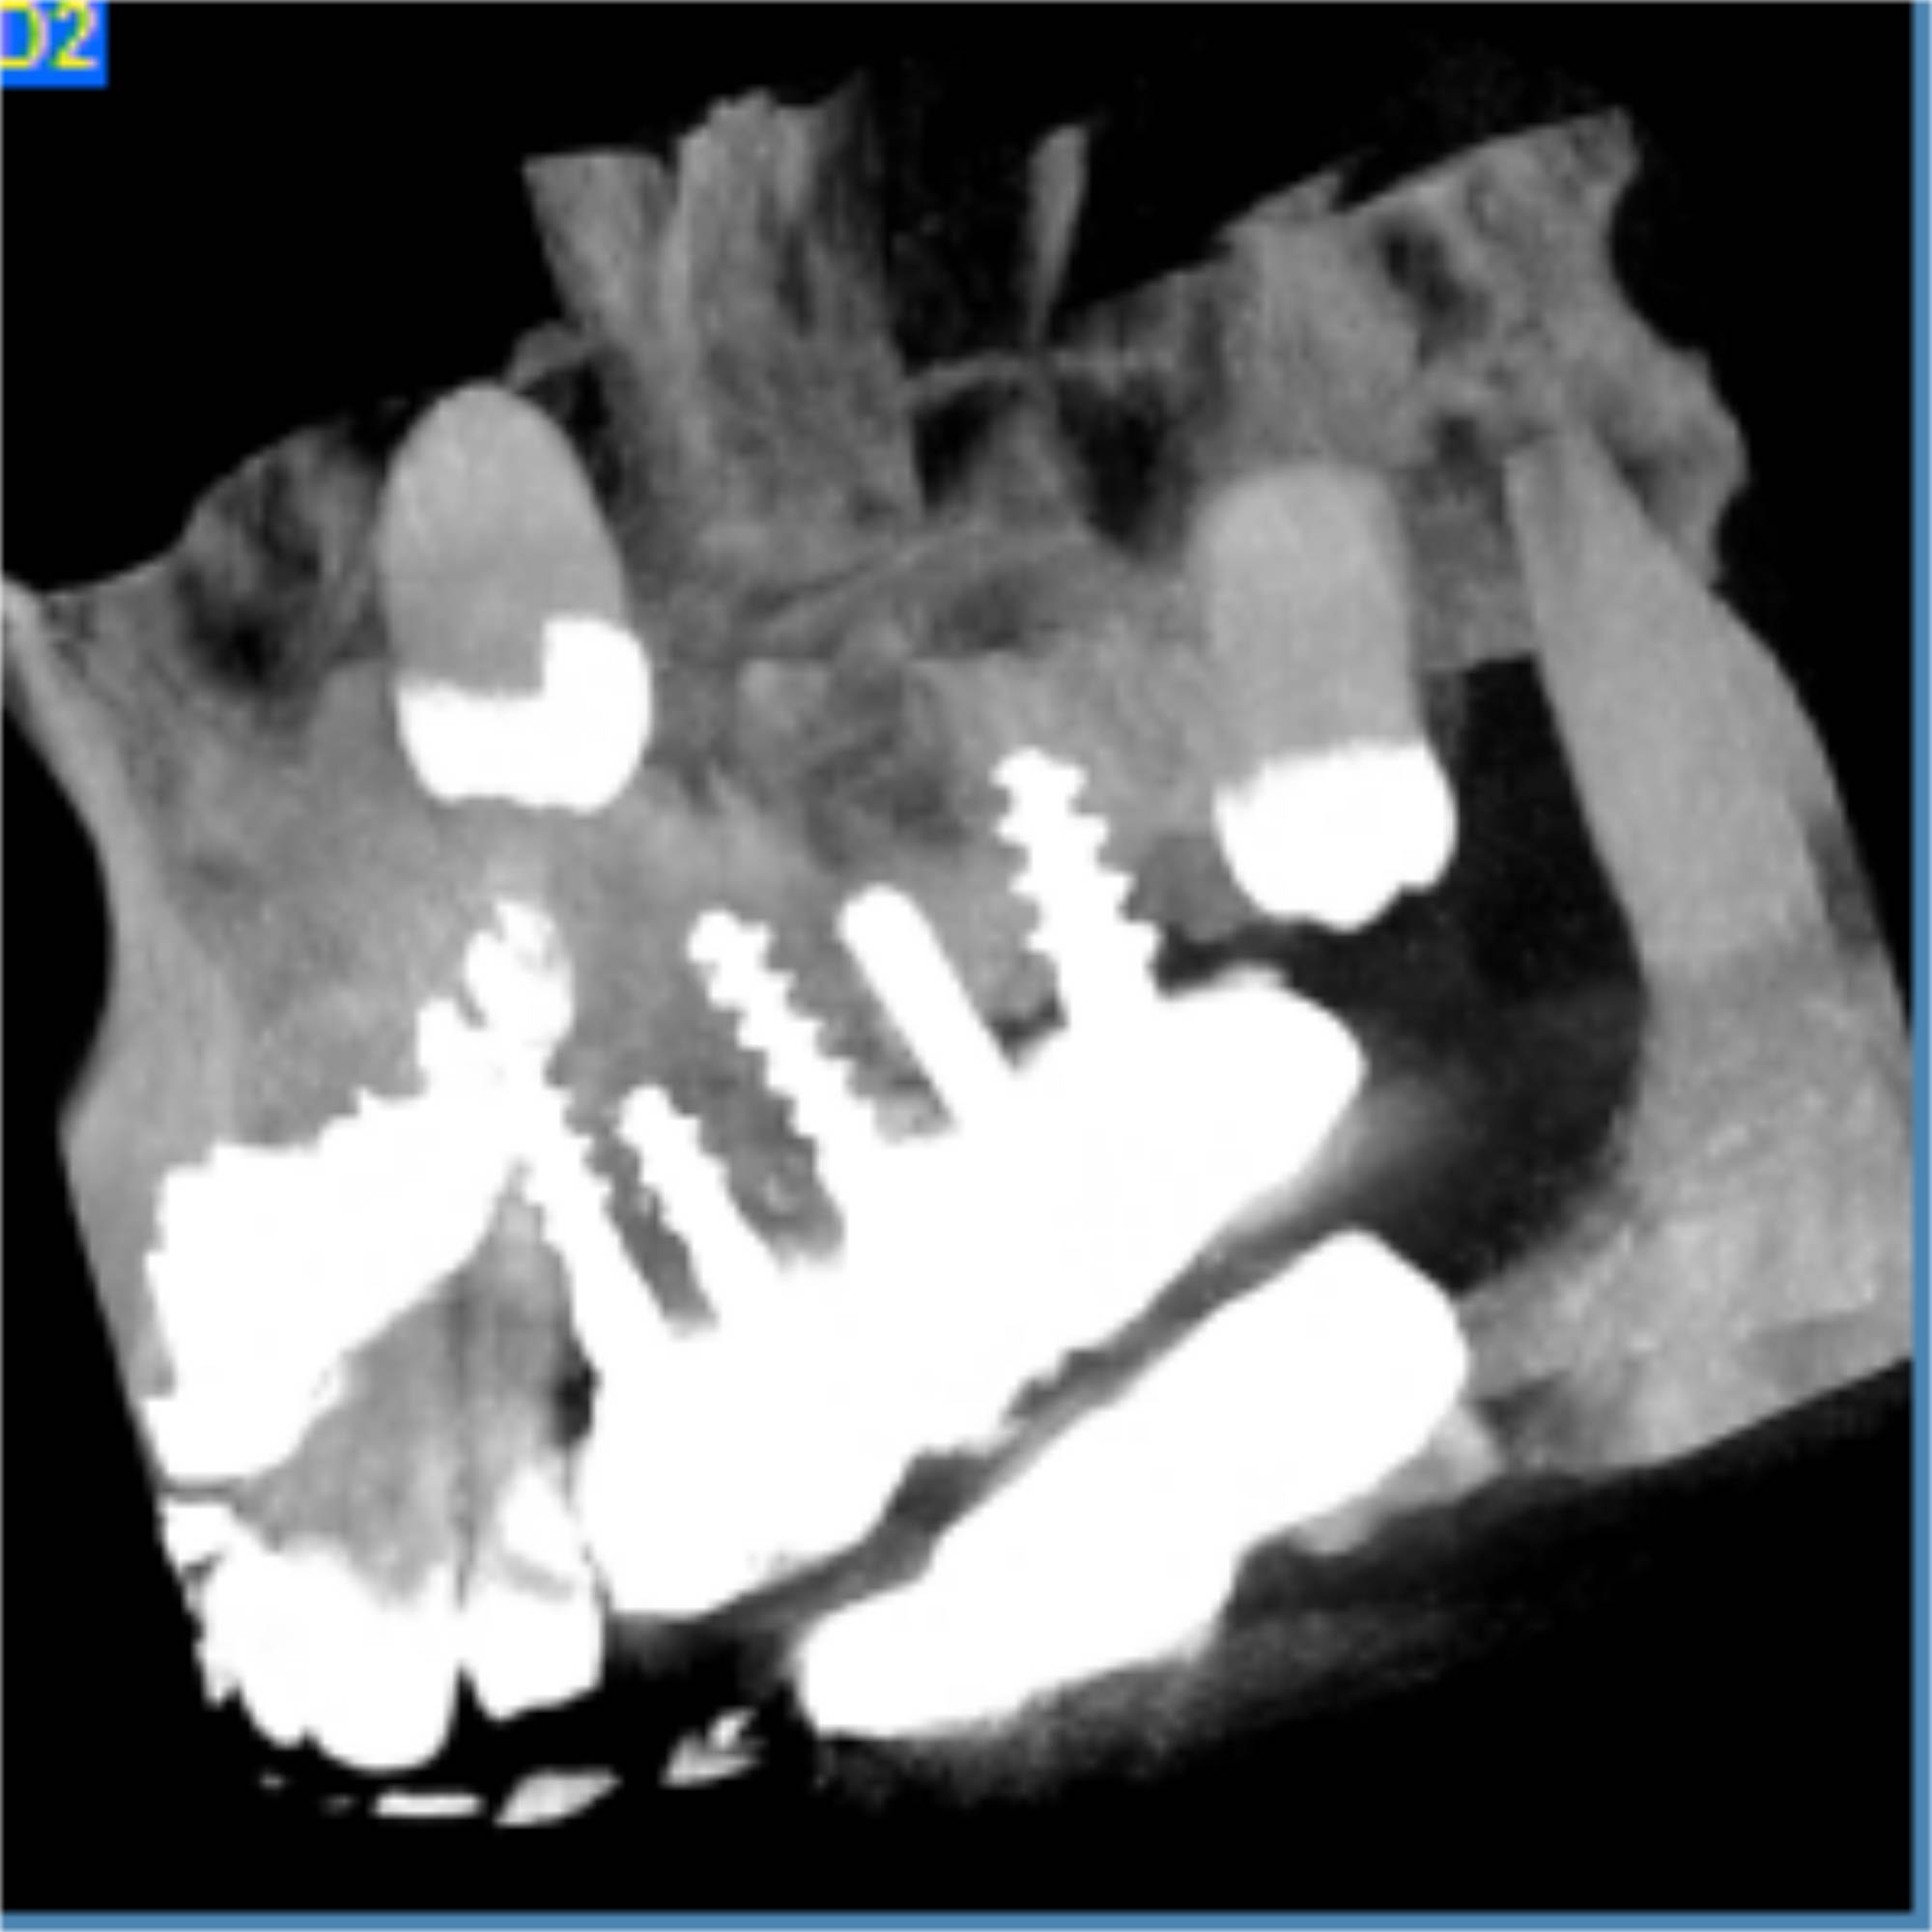

Hasta ahora, determinar el grado de osteointegración de un implante podía llegar a resultar complicado, ya que el artefacto metálico producido por elpropio implante no permitía ver con nitidez la zona.

Gracias a la tecnología CBCT con sus características de exposición y algoritmos de la reconstrucción de la imagen consiguen una disminución significativa del artefacto metálico en comparación con los TC convencionales.

De esta manera, el estudio por CBCT se vuelve imprescindible tanto para el estudio de planificación para implantología como para control de osteointegración una vez implantado.

Gracias a esta reducción casi total del artefacto metálico, el estudio por CBCT de la dentición no se ve prácticamente afectado por implantes o empastes que pueda portar el paciente.